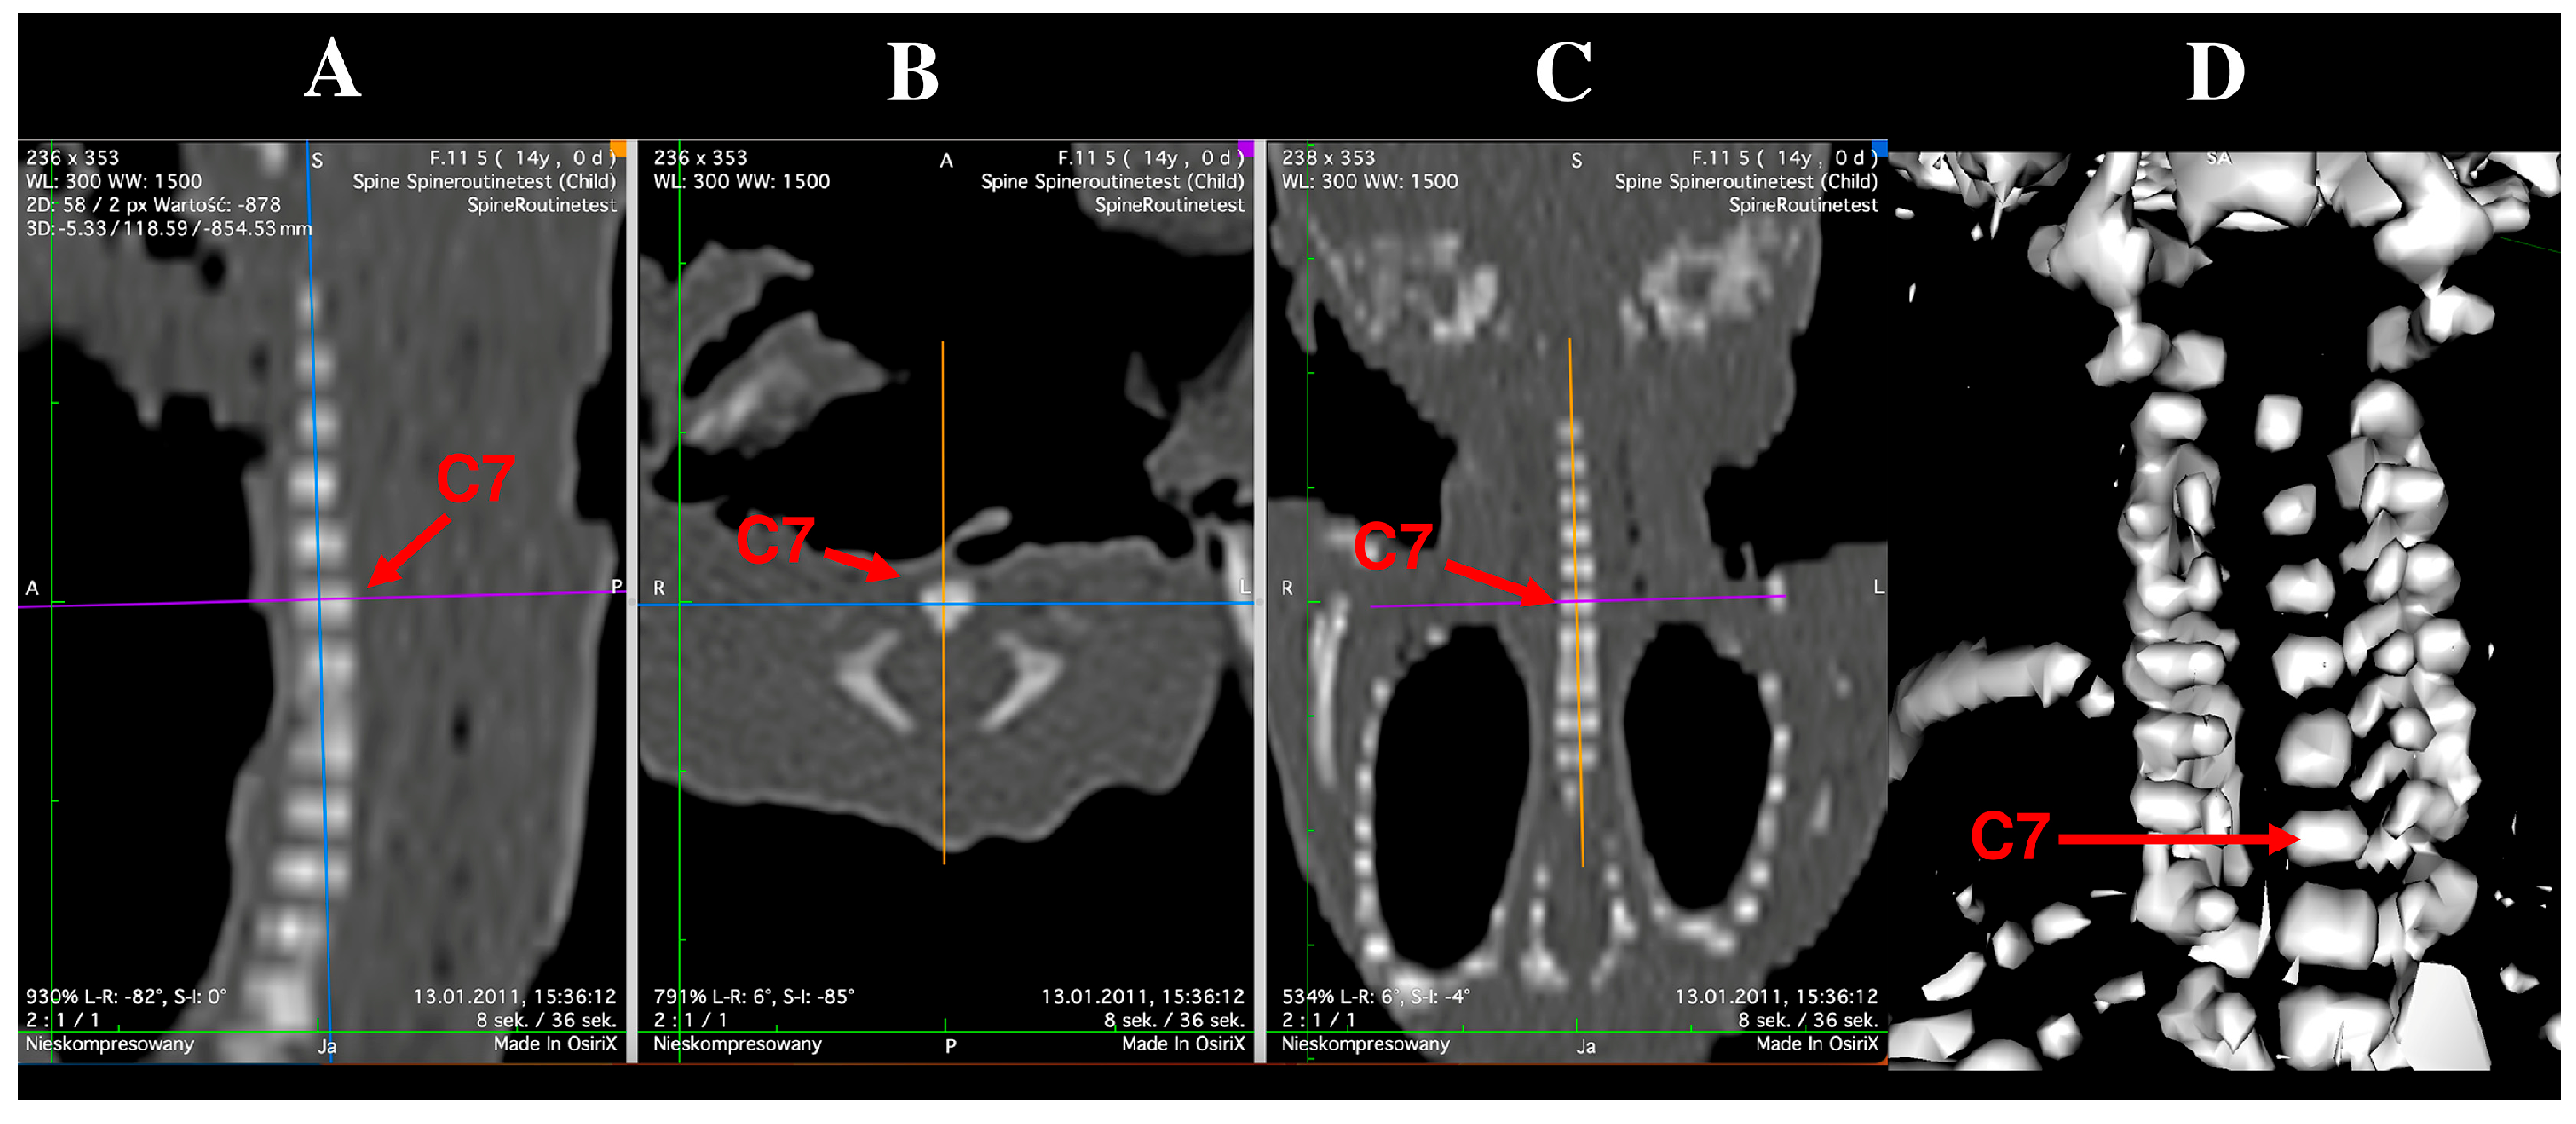

2.2. Morphometric Measurements and Assessment of Ossification Centers